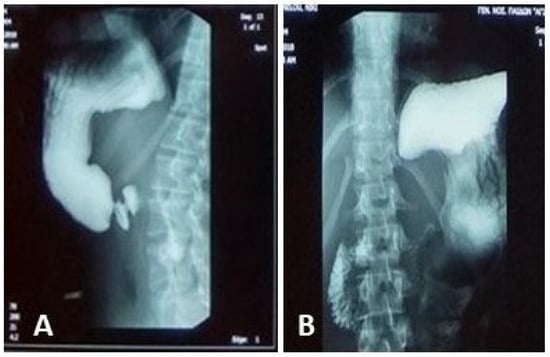

Persistent Vomiting and Epigastric Pain in an Adolescent: A Case of Superior Mesenteric Artery Syndrome Unmasked

Background and Clinical Significance: Superior mesenteric artery syndrome (SMAS) is a rare and often underdiagnosed cause of proximal intestinal obstruction, resulting from compression of the third portion of the duodenum between the SMA and the aorta. It typically occurs in individuals with significant [...] Read more.

Background and Clinical Significance: Superior mesenteric artery syndrome (SMAS) is a rare and often underdiagnosed cause of proximal intestinal obstruction, resulting from compression of the third portion of the duodenum between the SMA and the aorta. It typically occurs in individuals with significant weight loss due to mesenteric fat depletion. CasePresentation: We report the case of a 14.5-year-old female presented with a 6-day history of intractable vomiting and epigastric pain, on a background of intermittent vomiting over the preceding six months associated with a 7 kg unintentional weight loss, culminating in inability to tolerate oral intake. Her clinical course was complicated by a transient episode of blurred vision, numbness, and incoherent speech, initially suspected to be a neurological event. Extensive gastrointestinal and neurological investigations were inconclusive. Elevated fecal calprotectin levels raised suspicion for inflammatory bowel disease, given her family history, though endoscopy and histopathology were unremarkable. Advanced imaging ultimately demonstrated a markedly reduced aortomesenteric angle (6°) and distance (4 mm), confirming the diagnosis of SMAS. The patient was initially managed conservatively with total parenteral nutrition (TPN), achieving partial weight gain of 5 kg after 8 weeks of TPN. Due to persistent duodenal compression, surgical intervention was required. At 7-month follow-up, the patient remained symptom-free with restored nutritional status and a good weight gain. Conclusions: This case highlights the importance of considering SMAS in adolescents with chronic upper gastrointestinal symptoms and significant weight loss. Early recognition and appropriate imaging are essential to diagnosis, and timely surgical management can lead to excellent outcomes when conservative treatment is insufficient. Full article